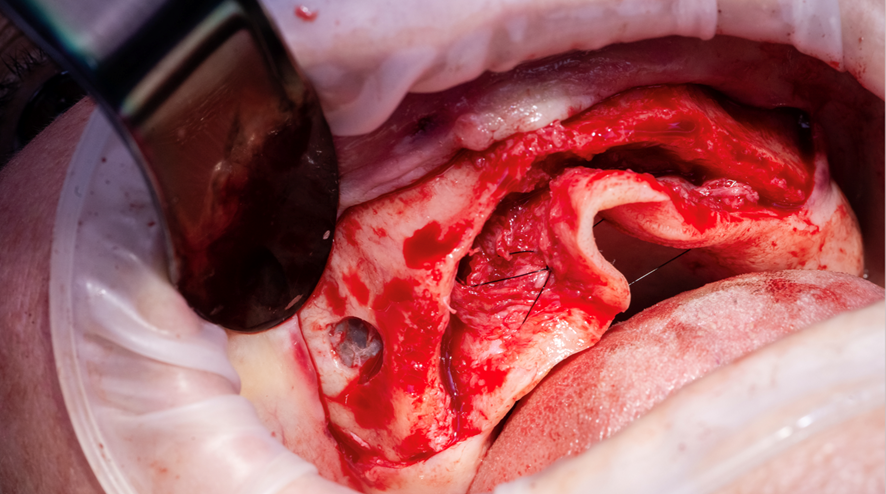

Após planejamento do caso, foi proposto e aceito pelo paciente a realização da reabilitação da maxila com quatro implantes, sendo dois implantes convencionais e dois transinusais. A publicação do caso foi autorizada mediante assinatura do Termo de Consentimento Livre Esclarecido (TCLE). Posteriormente à anestesia da maxila, foi realizado um retalho total e a janela lateral para acesso à parede anterior do seio (Figuras 2, 3 e 4). Após a osteotomia, a membrana foi cuidadosamente descolada no sentido anteroposterior.